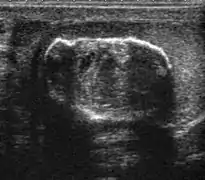

At ultrasound, the findings of acute epididymitis include an enlarged hypoechoic or hyperechoic (presumably secondary to hemorrhage) epididymis [Fig. 20a]. Other signs of inflammation such as increased vascularity, reactive hydrocele, pyocele and scrotal wall thickening may also be present. Testicular involvement is confirmed by the presence of testicular enlargement and an inhomogeneous echotexture. Hypervascularity on color Doppler images [Fig. 20b] is a well-established diagnostic criterion and may be the only imaging finding of epididymo-orchitis in some men.

Doppler ultrasound of epididymitis, seen as a substantial increase in blood flow in the left epididymis (top image), while it is normal in the right (bottom image). The thickness of the epididymis (between yellow crosses) is only slightly increased (7 mm).

Doppler ultrasound of the scrotum of the same case, in the axial plane, showing orchitis (as part of epididymo-orchitis) as hypoechogenic and slightly heterogenic left testicular tissue (right in image), with an increased blood flow. There is also swelling of peritesticular tissue.